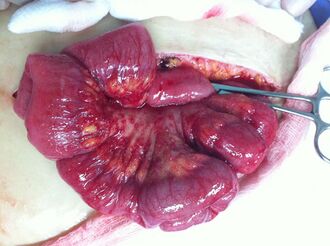

In advanced cancers, where complete removal is not an option, as much tumor as possible is removed in a procedure called debulking surgery. This surgery is not always successful, and is less likely to be successful in women with extensive metastases in the peritoneum, stage- IV disease, cancer in the transverse fissure of the liver, mesentery, or diaphragm, and large areas of ascites. Debulking surgery has usually only been done once[28] but a recent study has shown a longer overall survival in recurrent ovarian cancer when surgery combined with chemotherapy was performed compared to treatment with chemotherapy alone.[94] Computed tomography (abdominal CT) is often used to assess if primary debulking surgery is possible, but low certainty evidence also suggests fluorodeoxyglucose‐18 (FDG) PET/CT and MRI may be useful as an addition for assessing macroscopic incomplete debulking.[95] More complete debulking is associated with better outcomes: women with no macroscopic evidence of disease after debulking have a median survival of 39 months, as opposed to 17 months with less complete surgery.[26] By removing metastases, many cells that are resistant to chemotherapy are removed, and any clumps of cells that have died are also removed. This allows chemotherapy to better reach the remaining cancer cells, which are more likely to be fast-growing and therefore chemosensitive.[29]